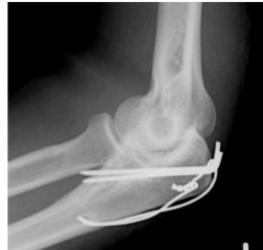

Tension-band Wires

- Indications:

- Patellar and olecranon fractures

- Possible to use in malleolar fractures

- Application:

- K-wires applied first, then tension-band wire